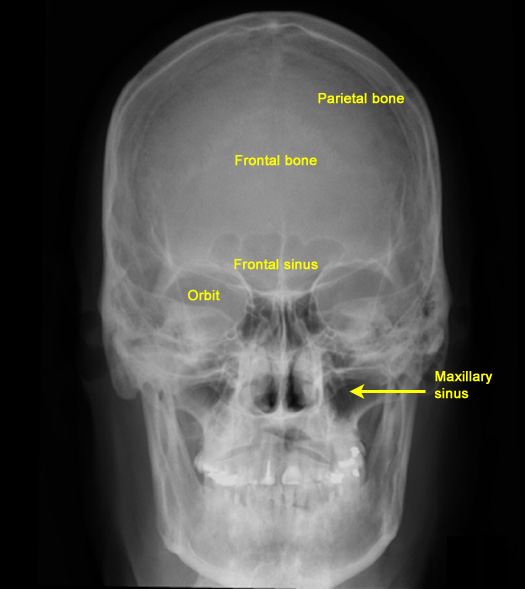

Plain Films of Skull and Spine